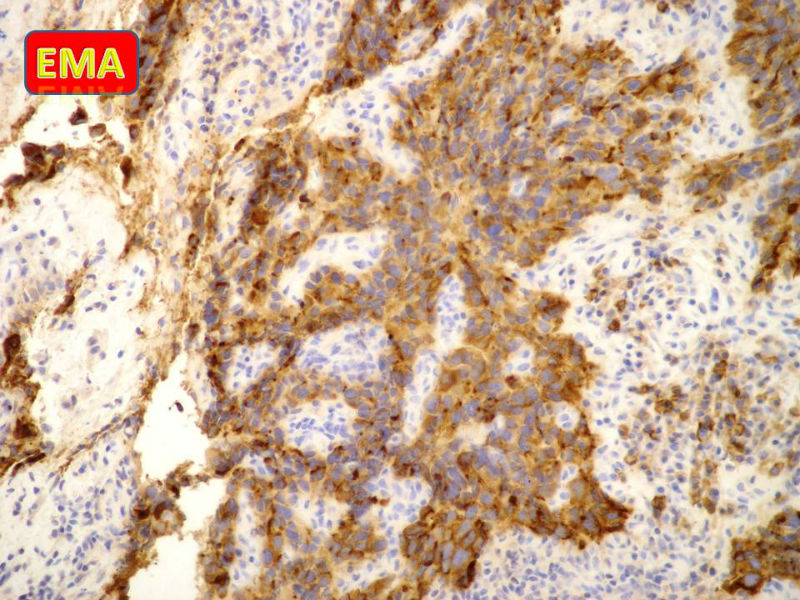

免疫组化